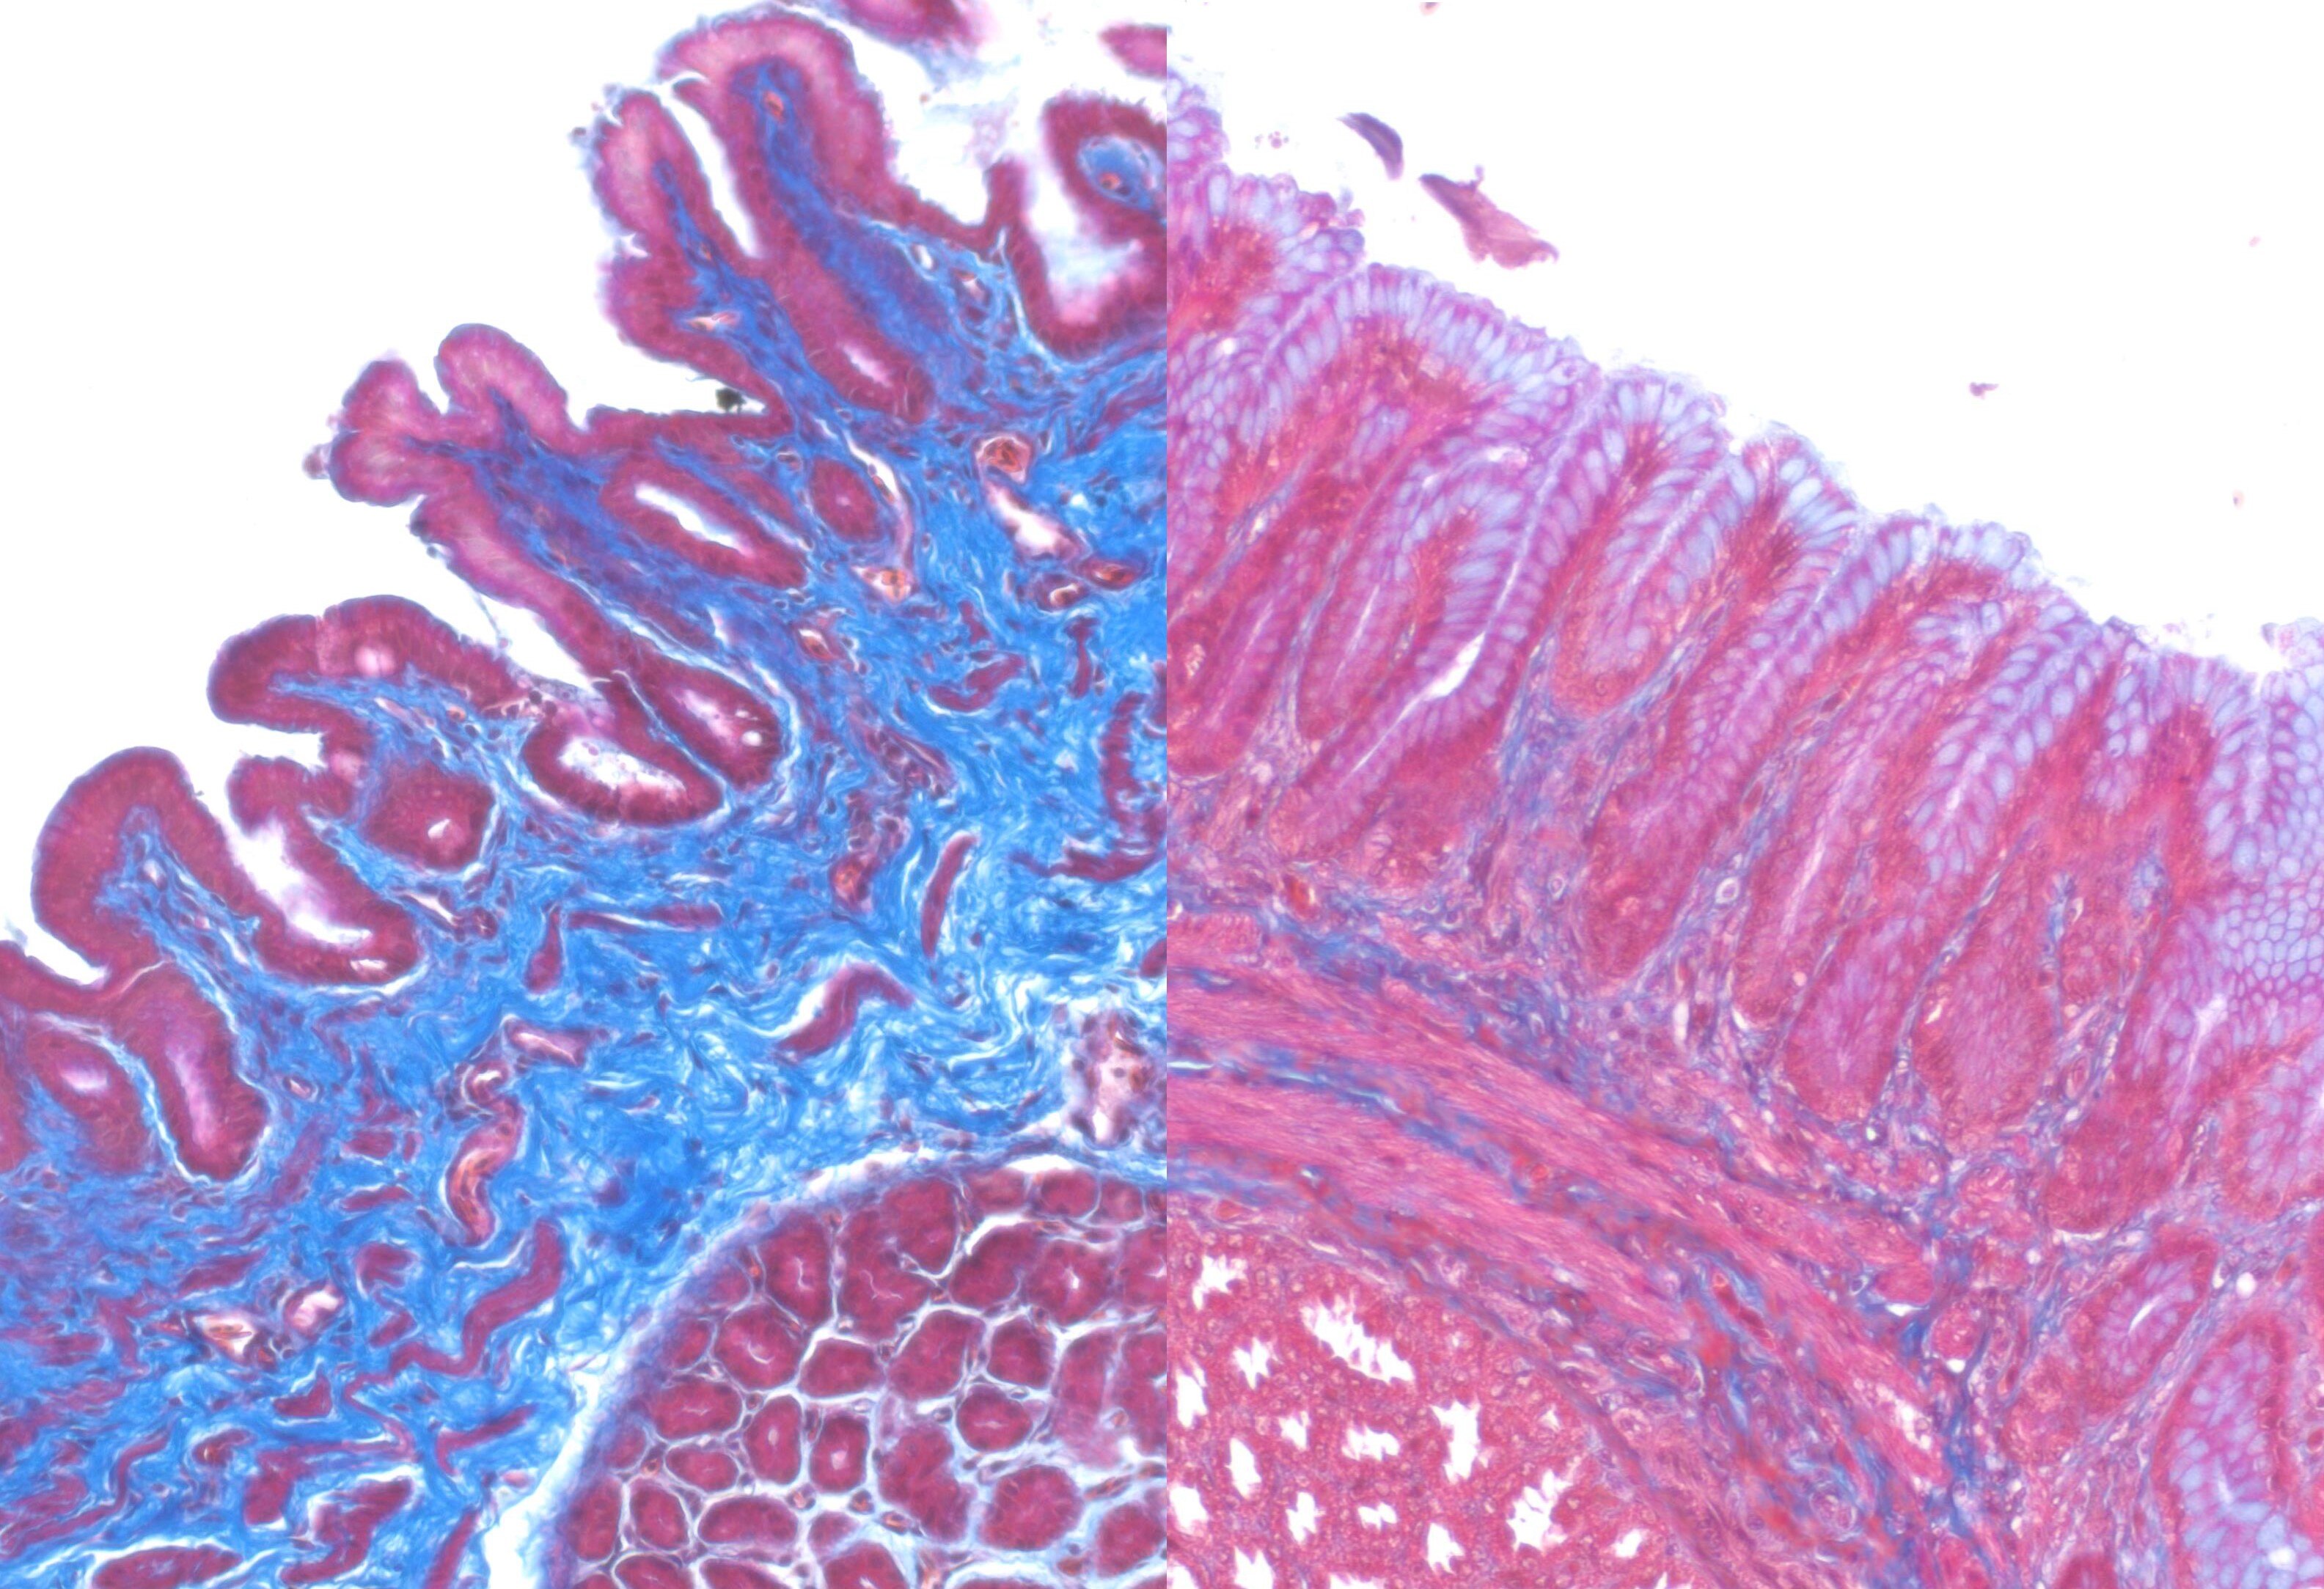

Tissue affected by plasticosis on the left, compared to healthy tissue on the right. (Supplied: Hayley Charlton-Howard)

Named plasticosis, the newly classified disease is caused by plastic that repeatedly injures soft tissue and leads to the formation of extensive scar tissue in a bird's stomach.

Impacted scar tissue does not operate like healthy tissue and can impact organ structure and function.